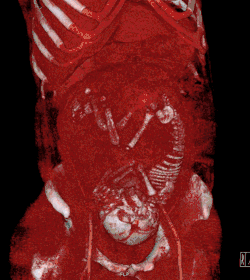

Creation of three-dimensional images

Volume rendering techniques have been developed to enable CT, MRI and ultrasound scanning software to produce 3D images for the physician.[43] Traditionally CT and MRI scans produced 2D static output on film. To produce 3D images, many scans are made and then combined by computers to produce a 3D model, which can then be manipulated by the physician. 3D ultrasounds are produced using a somewhat similar technique. In diagnosing disease of the viscera of the abdomen, ultrasound is particularly sensitive on imaging of biliary tract, urinary tract and female reproductive organs (ovary, fallopian tubes). As for example, diagnosis of gallstone by dilatation of common bile duct and stone in the common bile duct. With the ability to visualize important structures in great detail, 3D visualization methods are a valuable resource for the diagnosis and surgical treatment of many pathologies. It was a key resource for the famous, but ultimately unsuccessful attempt by Singaporean surgeons to separate Iranian twins Ladan and Laleh Bijani in 2003. The 3D equipment was used previously for similar operations with great success.